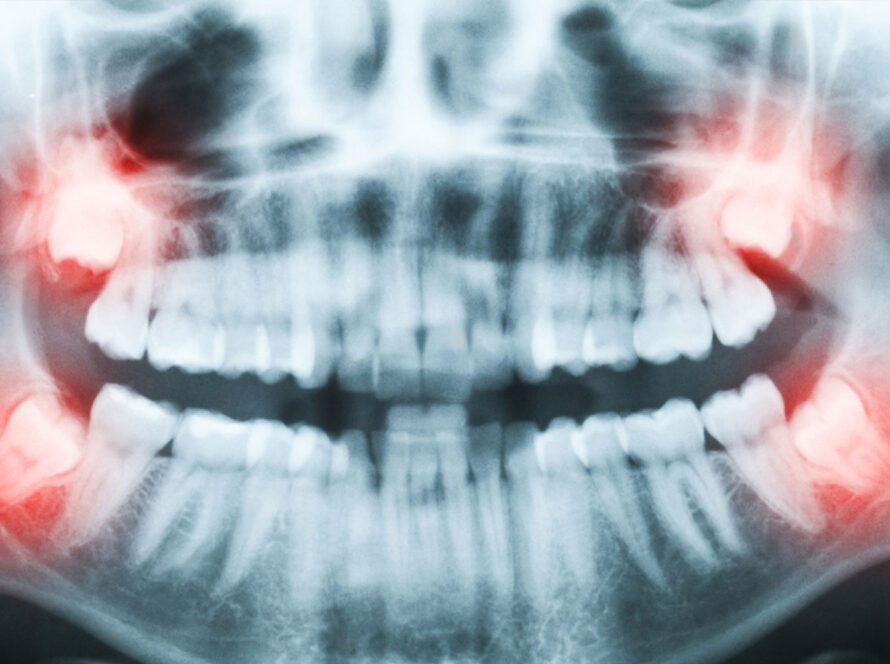

Top image used under CC0 Public Domain license. Image cropped and modified from original.